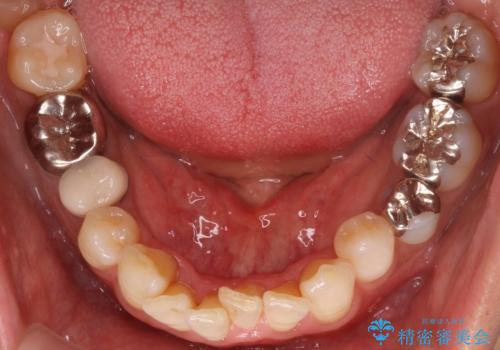

- 銀歯をすべてやり替えたいとのことで来院された患者様です。

再根管治療が必要なところは再根管治療から、そうでないところは補綴物のみをやり替えていくこととなりました。

銀歯のやり替えと並行してホワイトニングも行いました。

結果的には銀歯がすべて白くなり、前歯のガタつきもある程度改善され大変喜んでいただけました。